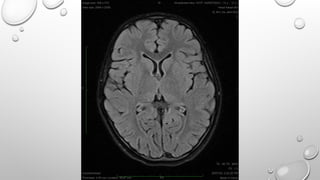

DIFFUSION WEIGHTED IMAGING

• FREE WATER MOLECULES ARE IN THE CONSTANT RANDOM MOTION KNOWN AS BROWNIAN

MOTION WHICH IS RELATED TO THERMAL KINETIC ENERGY. IN CONTRAST THERMALLY

INDUCED WATER MOVEMENT IN TISSUES IS NEITHER ENTIRELY FREE NOR RANDOM , IT IS

MODIFIED BY INTERACTIONS WITH CELL MEMBRANES, INTRACELLULAR ORGANELLES ,

MACROMOLECULES AND FLOWS WITHIN THE TUBULAR CHANNELS SUCH AS BLOOD VESSELS

AND DUCTS. THIS WATER DIFFISIUITY CAN BE MEASURED USING FAT SUPPRESSED T2

WEIGHTED SPIN ECHO SEQUENCE USING SINGLE SHOT ECHOPLANAR IMAGING.

DIFFUSION WEIGHTED IMAGING •FREE WATER MOLECULES ARE IN THE CONSTANT RANDOM MOTION KNOWN AS BROWNIAN MOTION WHICH IS RELATED TO THERMAL KINETIC ENERGY. IN CONTRAST THERMALLY INDUCED WATER MOVEMENT IN TISSUES IS NEITHER ENTIRELY FREE NOR RANDOM , IT IS MODIFIED BY INTERACTIONS WITH CELL MEMBRANES, INTRACELLULAR ORGANELLES , MACROMOLECULES AND FLOWS WITHIN THE TUBULAR CHANNELS SUCH AS BLOOD VESSELS AND DUCTS. THIS WATER DIFFISIUITY CAN BE MEASURED USING FAT SUPPRESSED T2 WEIGHTED SPIN ECHO SEQUENCE USING SINGLE SHOT ECHOPLANAR IMAGING.